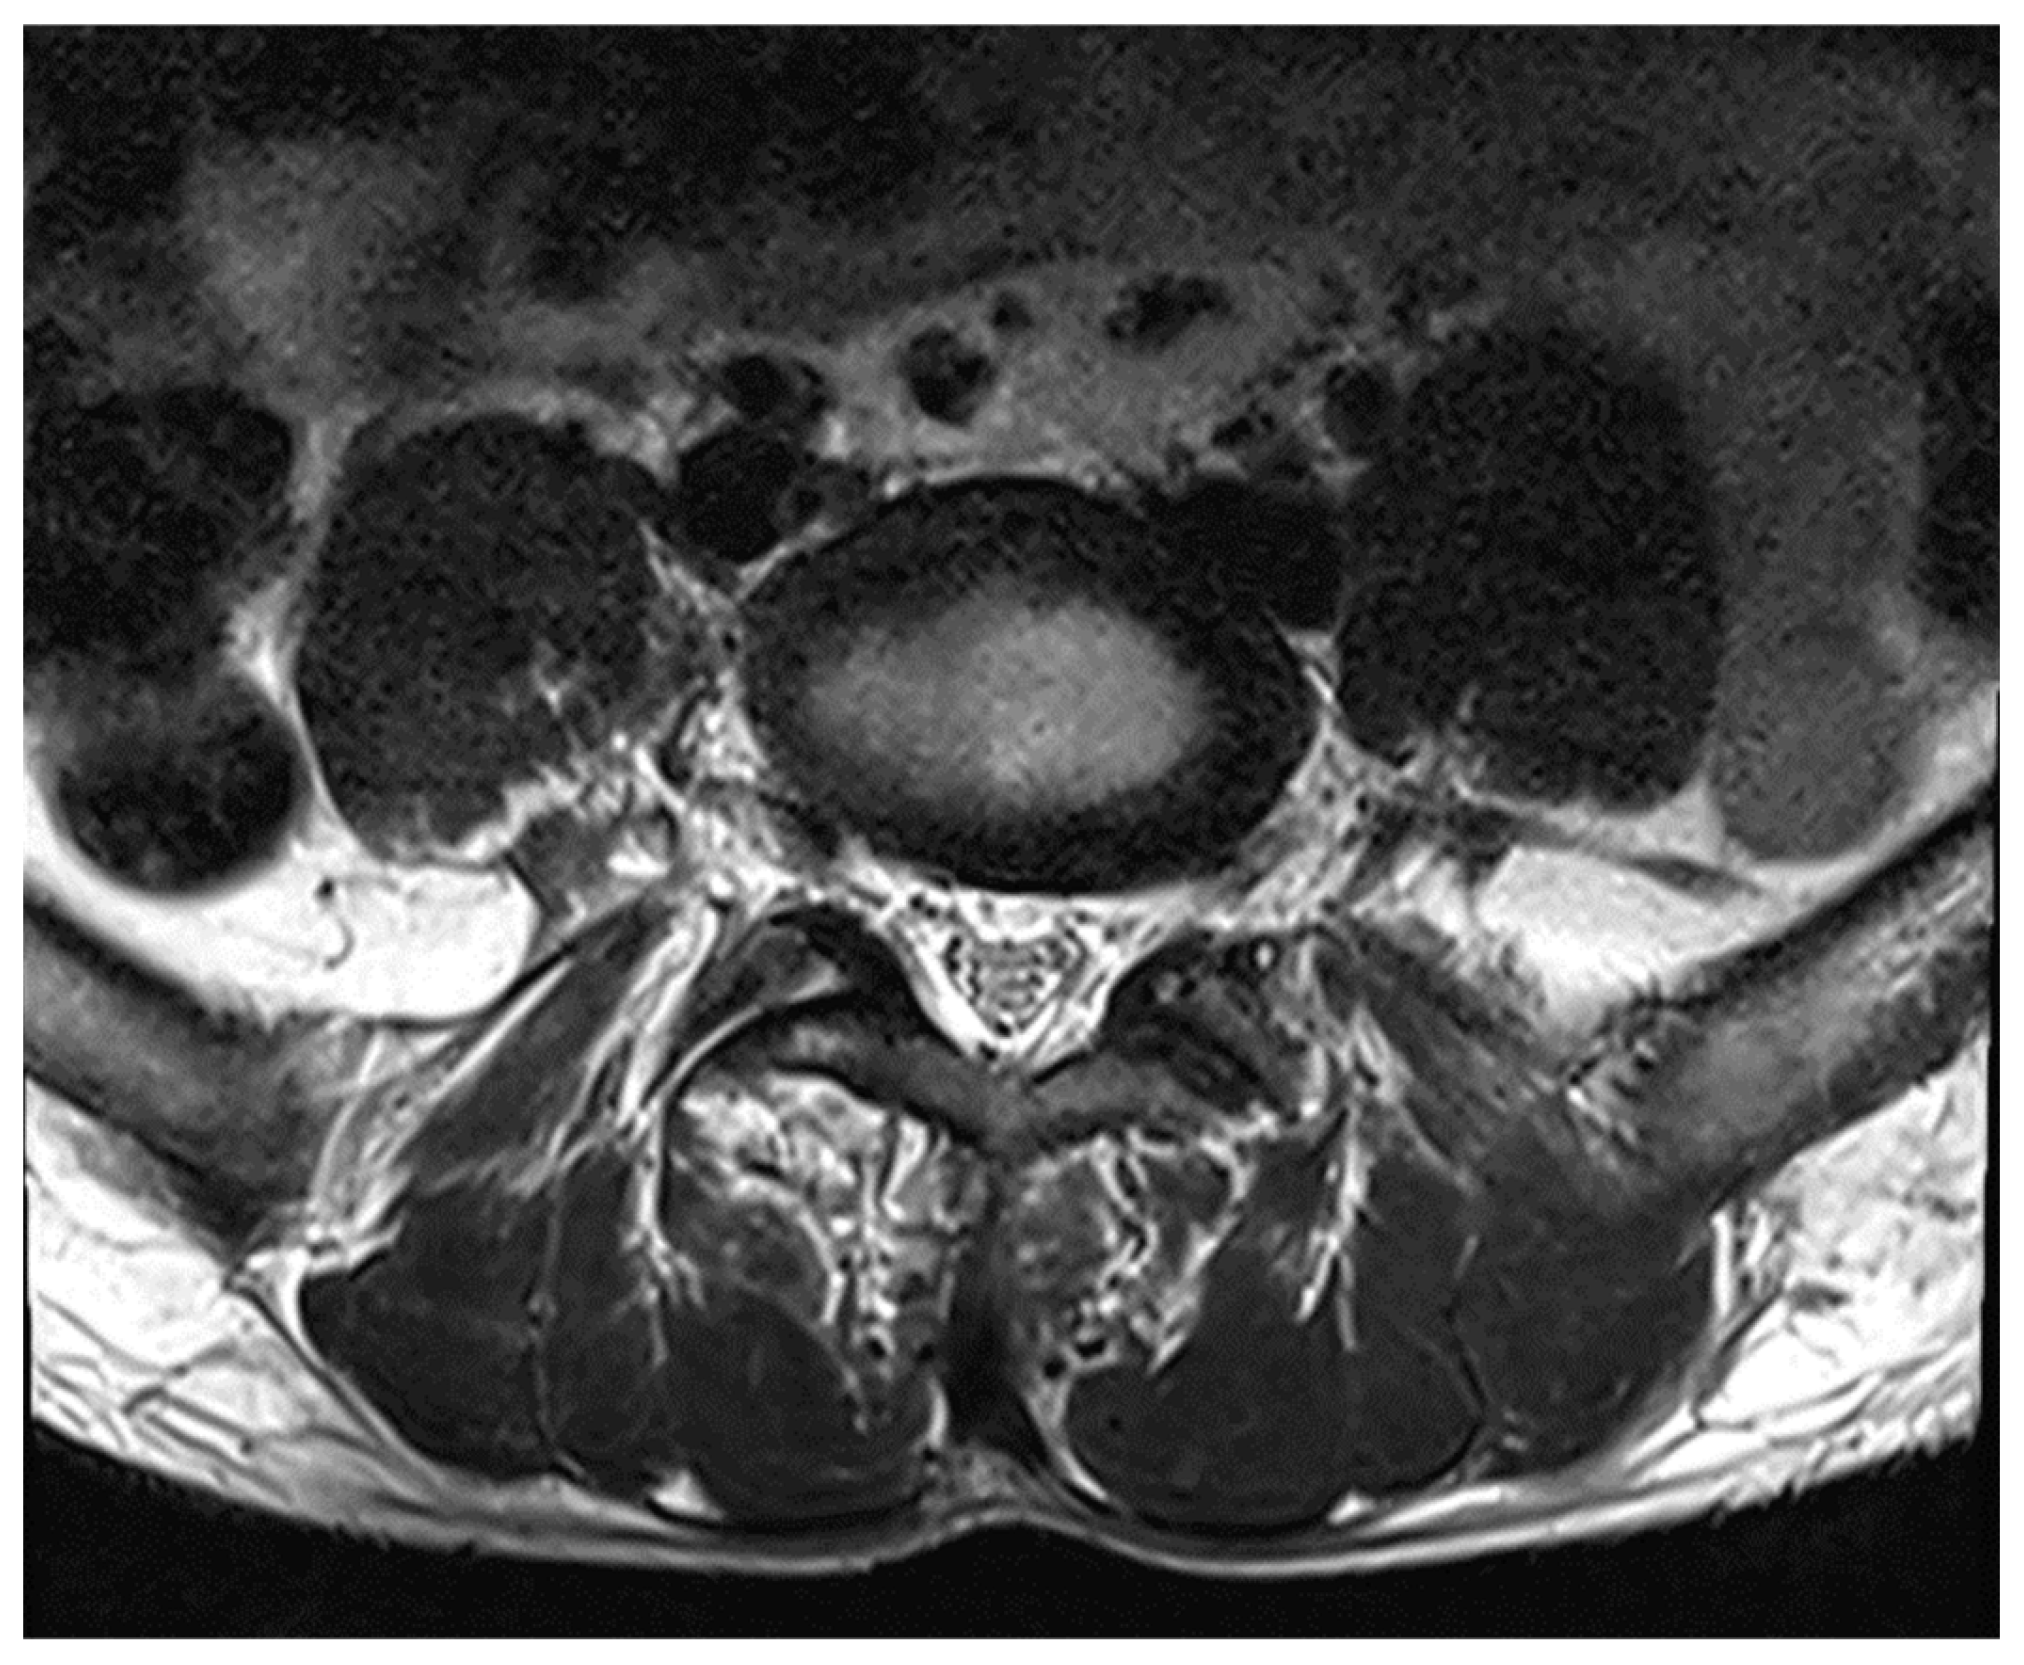

MRI whole spine screening showed early disc desiccation at upper cervical vertebral levels. Haemangioma was noted in the body of the D2 vertebra. C3-C4 level showed disc osteophytes complex causing indentation over anterior thecal sac without causing significant nerve root compression. Repeated MRI Spine showed an abutment over the right exiting nerve root at the above-mentioned level. L5-S1 level showed diffuse disc bulge causing bilateral lateral recess stenosis, neural foraminal narrowing and indentation over the anterior thecal sac with resultant abutment over bilateral exiting nerve roots. Above-stated findings give evidence of demyelinating Balo’s Concentric Sclerosis.

Figure 6. MRI spine L5-S1 level.

Figure 7. MRI Spine Axial Section.